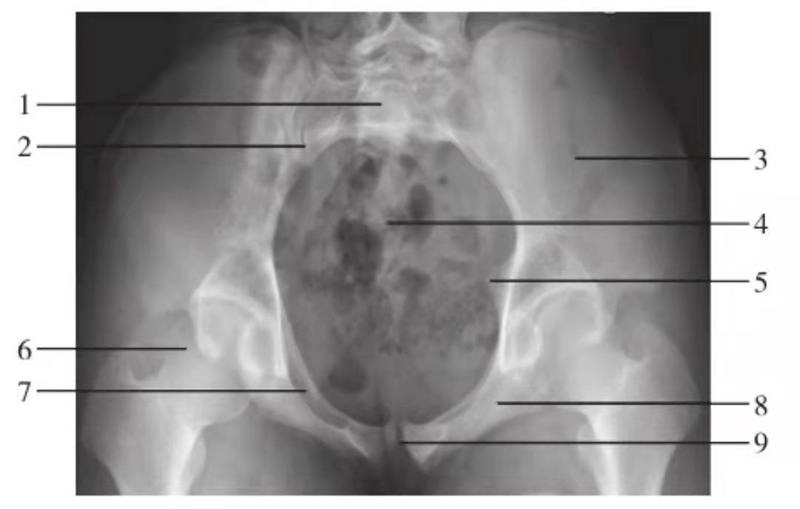

骨盆入口位

图7 骨盆入口位

1.骶骨;2.骶髂关节;3.髂骨翼;4.尾骨;5.坐骨棘;6.股骨头;7.耻骨上支;8.坐骨支;9.耻骨联合